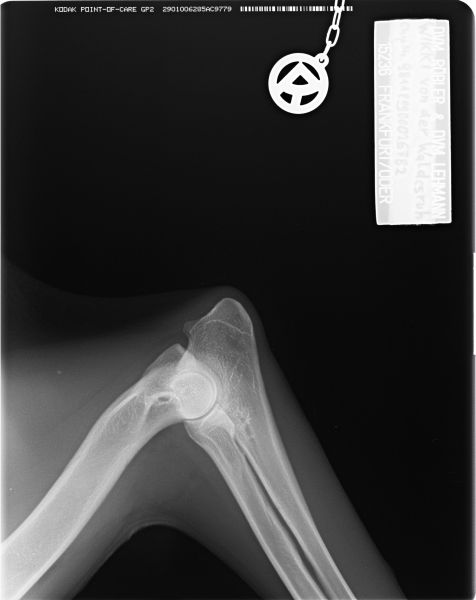

Auswertung der Röntgenbilder von Wikki  aus Augsburg:

HD- fast normal; ED-normal